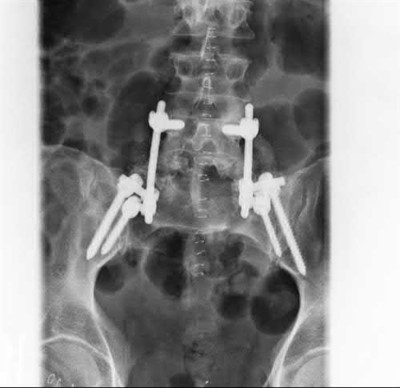

A 76-year-old male community ambulatory presented to clinic complaining of pain in the left groin that has been persistent for the last 8 months. Radiographs obtained from clinic are seen in Figure A. You suspect a femoral neck nonunion and obtain a CT scan which confirmed it. Which of the following statements is true?

A total hip arthroplasty (THA) after nonunion of a femoral neck fracture would provide the best long term outcomes in a 76-year-old male who is a community ambulator.

After nonunion of a femoral neck fracture, hemiarthroplasty and THA are good salvage option for the physiologically older patients. When deciding between these two options, THA is better for active and cognitively intact patients. THA is also indicated in patients with radiographic evidence of degenerative disease about the acetabulum. Hemiarthroplasty is advocated for patients who are older and less active.

Yang et al. retrospectively investigated the risk factors for nonunion in patients treated with cannulated screws. They reviewed 202 patients who had femoral neck fractures and were treated with internal fixation with cannulated screws. They identified that triangle configuration, displaced fracture, borderline or unacceptable reduction, and increased screw shaft subchondral purchase over the femoral neck were all risk factors for nonunion after internal fixation.

Inverted triangle configuration was found to increase rate of union.

Archibeck et al. retrospectively reviewed the outcomes of 102 THAs after failed internal fixation for a hip fracture (including both femoral neck and intertrochanteric). They concluded that the conversion of failed hip internal fixation has elevated risks compared to a primary THA, however, it may still be successful. The biggest concern for these patients postoperatively are periprosthetic fracture and dislocation.

Figures and Illustrations:

Figure A is an AP pelvic radiograph demonstrating a nonunion of a femoral neck fracture after suboptimal fixation with 3 cannulated screws in a triangle configuration.

Illustration A is an AP radiograph of the left hip in this patient following conversion to THA.

Illustration B is a radiograph demonstrating a valgus osteotomy. Illustration C shows an example of a femoral neck nonunion with varus malreduction.

Incorrect Answers:

Answer 2: Varus reduction is closely correlated with failure in this fixation method.

Answer 3: The patient's best outcome would be with THA.

Answer 4: This would be a good option in a younger patient, but given age and functional capacity, the best option is THA.

Answer 5: Patients with hemiarthroplasty have lower rates of dislocation.